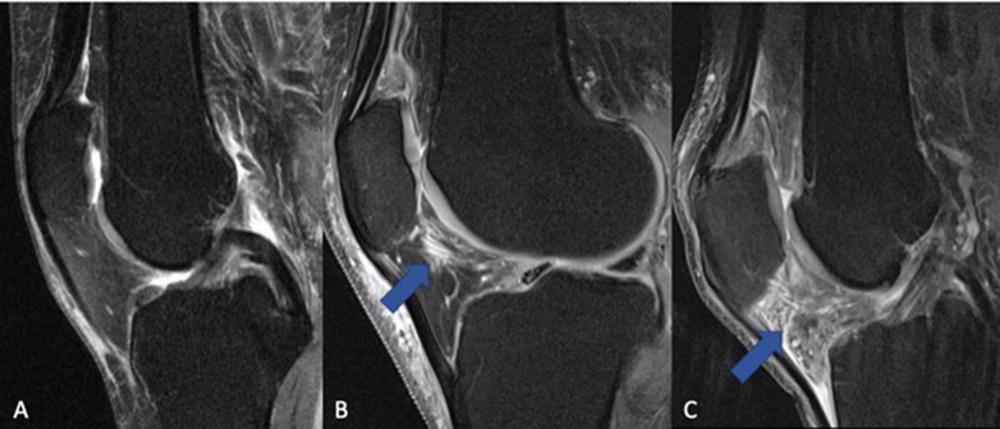

Para el estudio, se incluyeron 277 participantes de la cohorte de la Iniciativa de artrosis con artrosis de moderada a grave y tratamiento sostenido con AINE durante al menos un año entre el inicio y el seguimiento de cuatro años, y se compararon con un grupo de 793 participantes de control que no fueron tratados con AINE. Todos los participantes se sometieron a una resonancia magnética de 3T de la rodilla inicialmente y después de cuatro años. Las imágenes se puntuaron en busca de biomarcadores de inflamación.

El grosor del cartílago, la composición y otras mediciones de la IRM sirvieron como biomarcadores no invasivos para evaluar la progresión de la artritis.

Los resultados no mostraron ningún beneficio a largo plazo del uso de AINE. La inflamación de las articulaciones y la calidad del cartílago eran peores al inicio en los participantes que tomaban AINE, en comparación con el grupo de control, y empeoraron en el seguimiento de cuatro años.